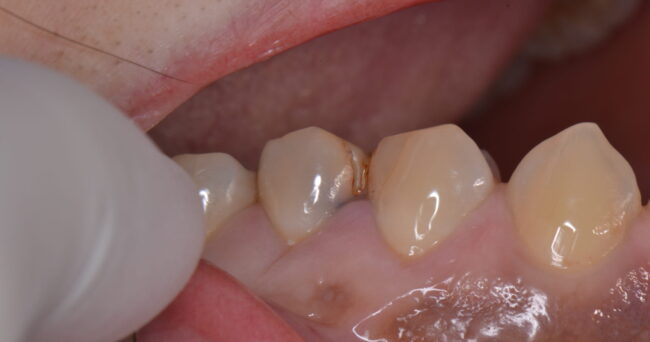

こちらの伝えたいことは変わりません。この形のものは外から見るとわからないが、縁から菌が侵入しやすい、というものです。

特に↓のような、境目がはっきりしている場合に、内側がやられているという状況はよくあります。

外すと、中はこのようになっていました。